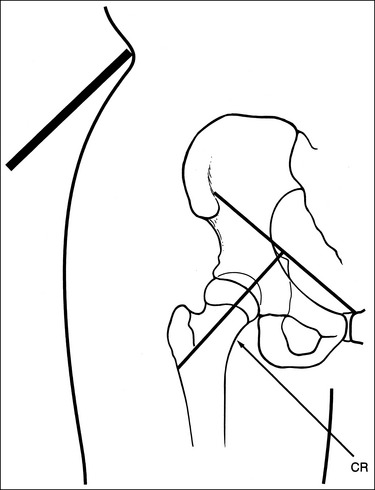

• Localizing the femoral neck for central ray alignment. To localize the affected femoral neck, first find the center of an imaginary line drawn between the superior symphysis pubis and the ASIS. Then, bisect that line by drawing a perpendicular line distally (Figure 7-17). This imaginary line parallels the long axis of the femoral neck as long as the leg is not abducted. Once the long axis of the femoral neck has been located, align the central ray perpendicular to it and the IR parallel with it.

FIGURE 7-17 Locating the femoral neck and proper image receptor placement for small and average patients.